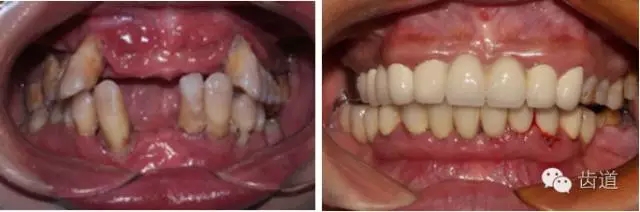

1.webp.jpg

2.webp.jpg

牙石及不良修復(fù)體

3.webp.jpg

4.webp.jpg